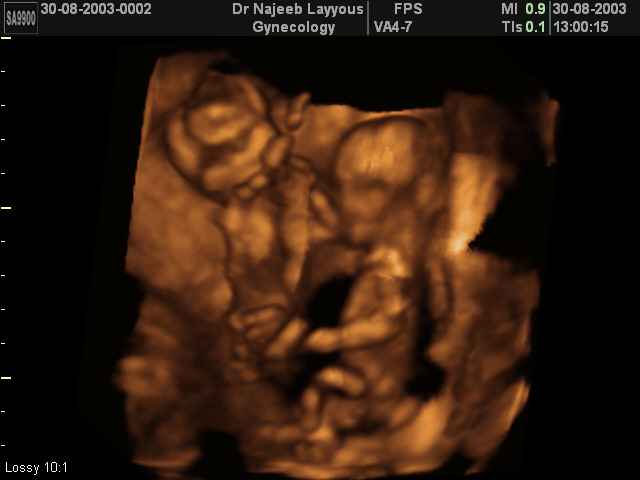

3D Photos échographie de grossesse multiple : Jumeaux, triplés et quadruples| Dr N Layyous

3D Photos échographie de grossesse multiple